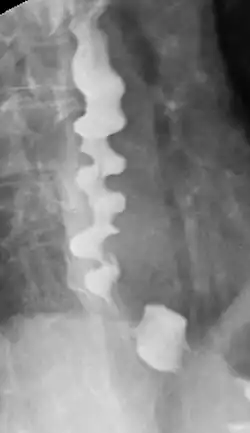

Certain abnormalities on x-ray imaging are commonly observed in DES, such as a "corkscrew esophagus" or "rosary bead esophagus", although these findings are not unique to this condition. Specialized testing called manometry can be performed to evaluate the motor function of the esophagus, which can help identify abnormal patterns of muscle contraction within the esophagus that are suggestive of DES. The treatment of DES consists primarily of medications, such as acid suppressing agents (like proton-pump inhibitors), calcium channel blockers, hyoscine butylbromide, or nitrates. In only extremely rare cases, surgery may be considered. People with DES have higher incidences of gastroesophageal reflux disease (GERD), neuromuscular diseases, and degenerative neurological disorders.

Several radiographic findings are suggestive of DES, such as a "corkscrew esophagus" or "rosary bead esophagus" appearance on barium swallow x-ray, although these findings are not unique to DES.[2]